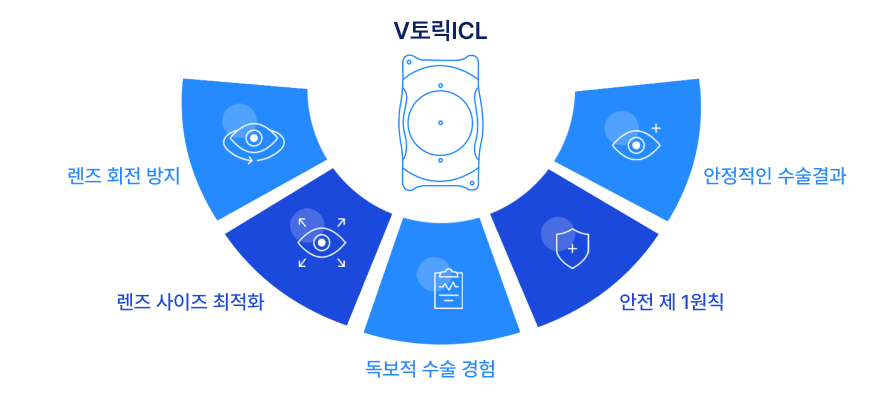

V 토릭 ICL

고도근시, 고도난시를 위한 새로운 기준

난시교정 V-토릭ICL

국내 난시교정 ICL의 70%는 렌즈 회전을 방지하기 위해 렌즈 사이즈를 키워 눈에 꽉 끼는 렌즈를 삽입하고 있습니다.

이 방법이 당장은 문제가 없더라도 10년 이상 기간이 지났을 때 생길 부작용까지 고민이 필요했습니다.

2002년 국내 처음 렌즈삽입술이 도입된 1세대 렌즈삽입술부터 1만 시간의 법칙을 상회하는 6만 건 증례 이상의 임상경험을 토대로

밝은세상안과만의 난시교정 알고리즘을 완성, 렌즈삽입술 분야에서 세계적 표준 V-토릭 ICL로 한 단계 더 앞서갑니다.

난시교정용 렌즈(Toric ICL)를 사용하여 수술하더라도 렌즈가 회전하게 되면 난시 축 변화가 생기게 되고

이는 전혀 다른 도수의 렌즈를 넣는 것처럼 모든 거리의 시력 저하를 초래합니다.

렌즈 사이즈를 키우지 않아도 렌즈 회전율을 최소화하여

근시와 난시교정 효과가 뛰어난

본원만의 혁신적인 렌즈삽입술입니다.

수술을 설계하여 난시가 동반된 고도 근시 교정 수술 대상자의 수술결과 만족도를 높이고 장기적으로

안정적인 시력이 유지됩니다.